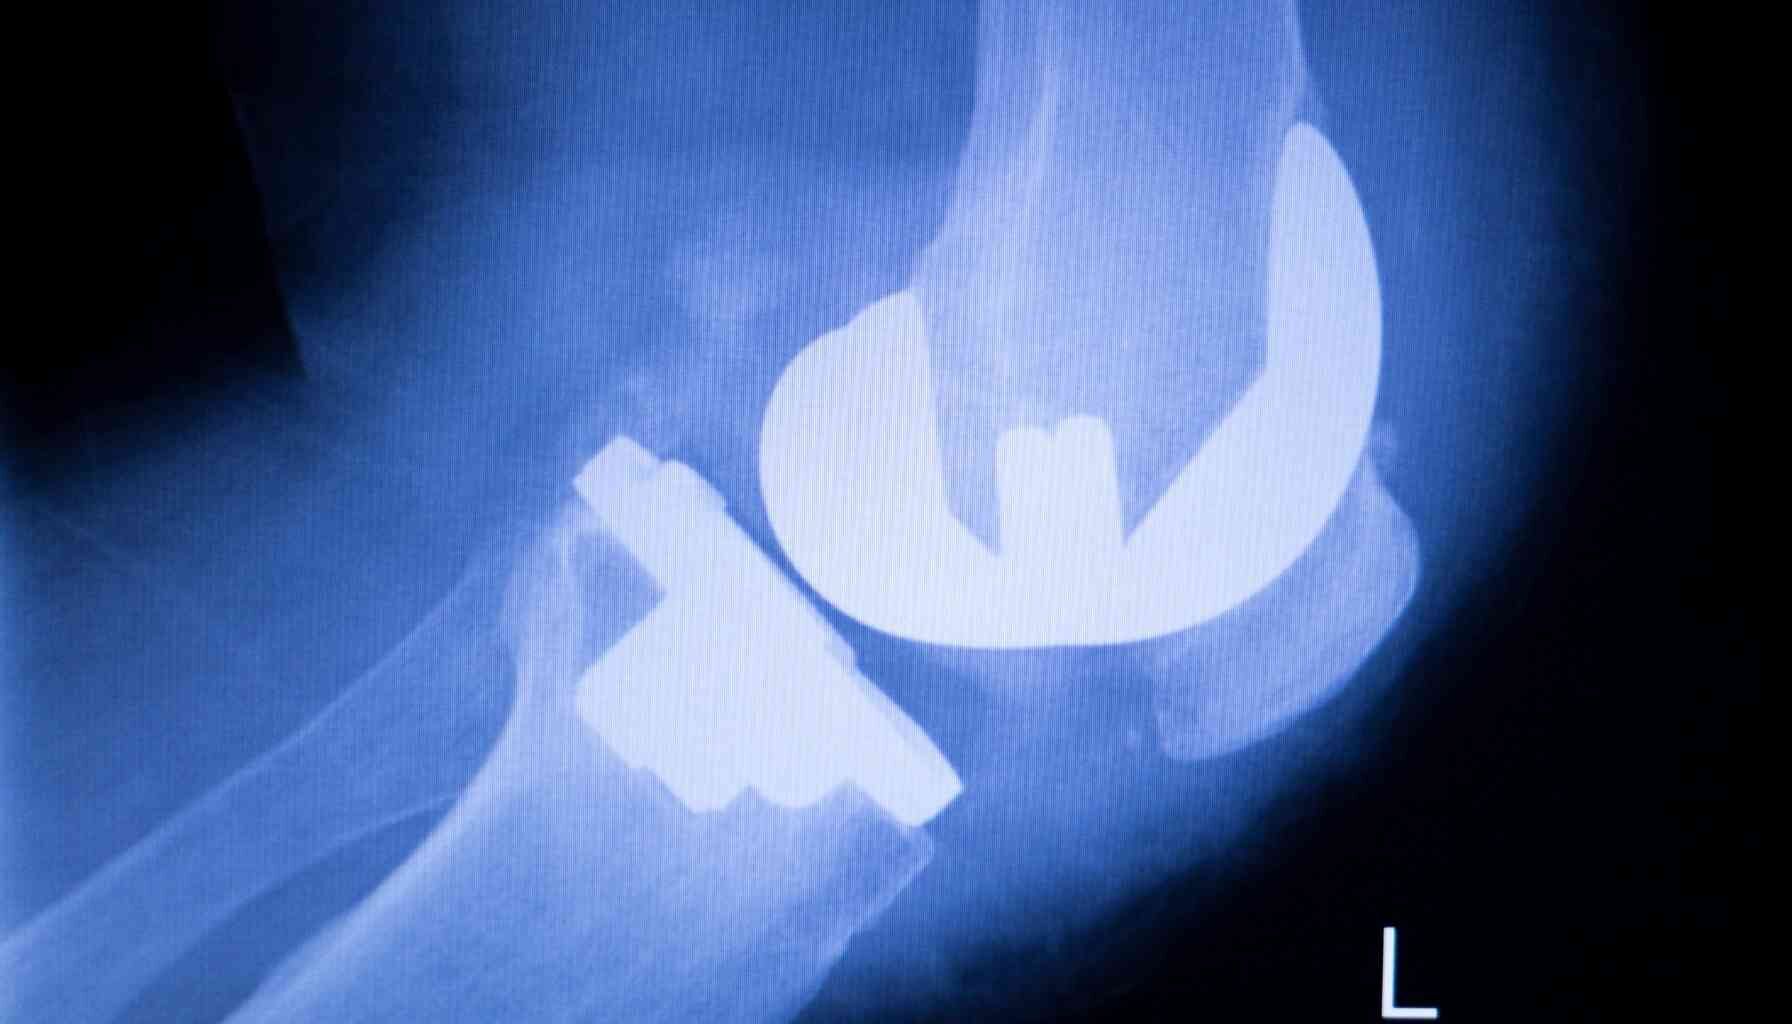

- Device Implantation: A specialized orthopedic device—either an external fixator or, more commonly today, an internal telescopic nail like the PRECICE nail—is implanted to stabilize the two bone segments.

- The Distraction Phase: After a short initial healing period, the device is used to very slowly separate the two bone segments, typically at a rate of about 1 millimeter per day.

- Bone Regeneration: As the segments are gradually pulled apart, the body responds by filling the gap with new bone tissue.

- The Consolidation Phase: Once the desired length is achieved, the distraction stops, and the new bone is allowed to harden and mature, a process that can take several months.